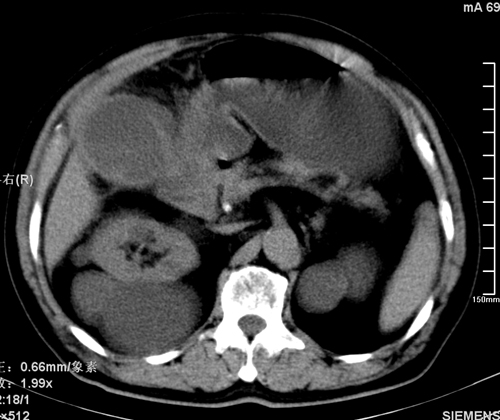

以下是引用liaoqiang在2008-3-27 15:57:00的发言:[br]1右肾脏周多发大小不一球形影,考虑肾脏囊肿可能性大。2胆囊边界欠清楚。考虑胆囊炎可能性。

以下是引用随光逐影在2008-3-27 16:33:00的发言:[br]考虑为:1)双肾囊肿可能。2)急性胆囊炎。建议:行进一步检查。